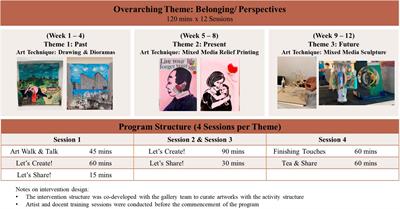

Effects of participatory ‘A’rt-Based Activity On ‘Health’ of Older Community-Dwellers: results from a randomized control trial of the Singapore A-Health Intervention